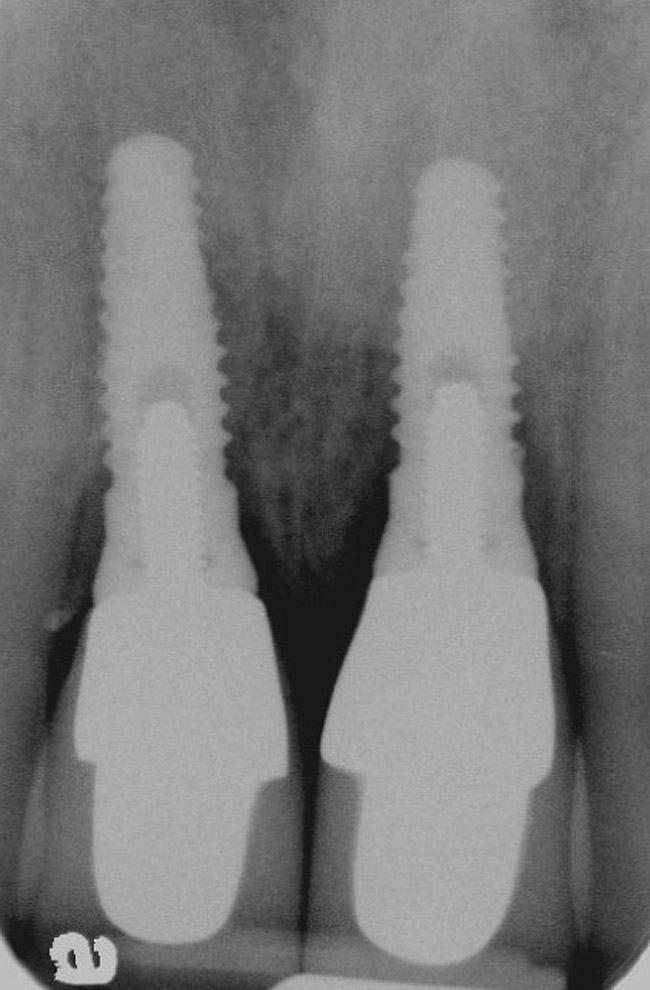

Figure 3  Periapical radiograph of implants in the Nos. 8 and 9 sites 3 years after placement. A bony peak was still present between the implants due to successful guided bone regeneration and favorable fixture spacing.

Figure 3